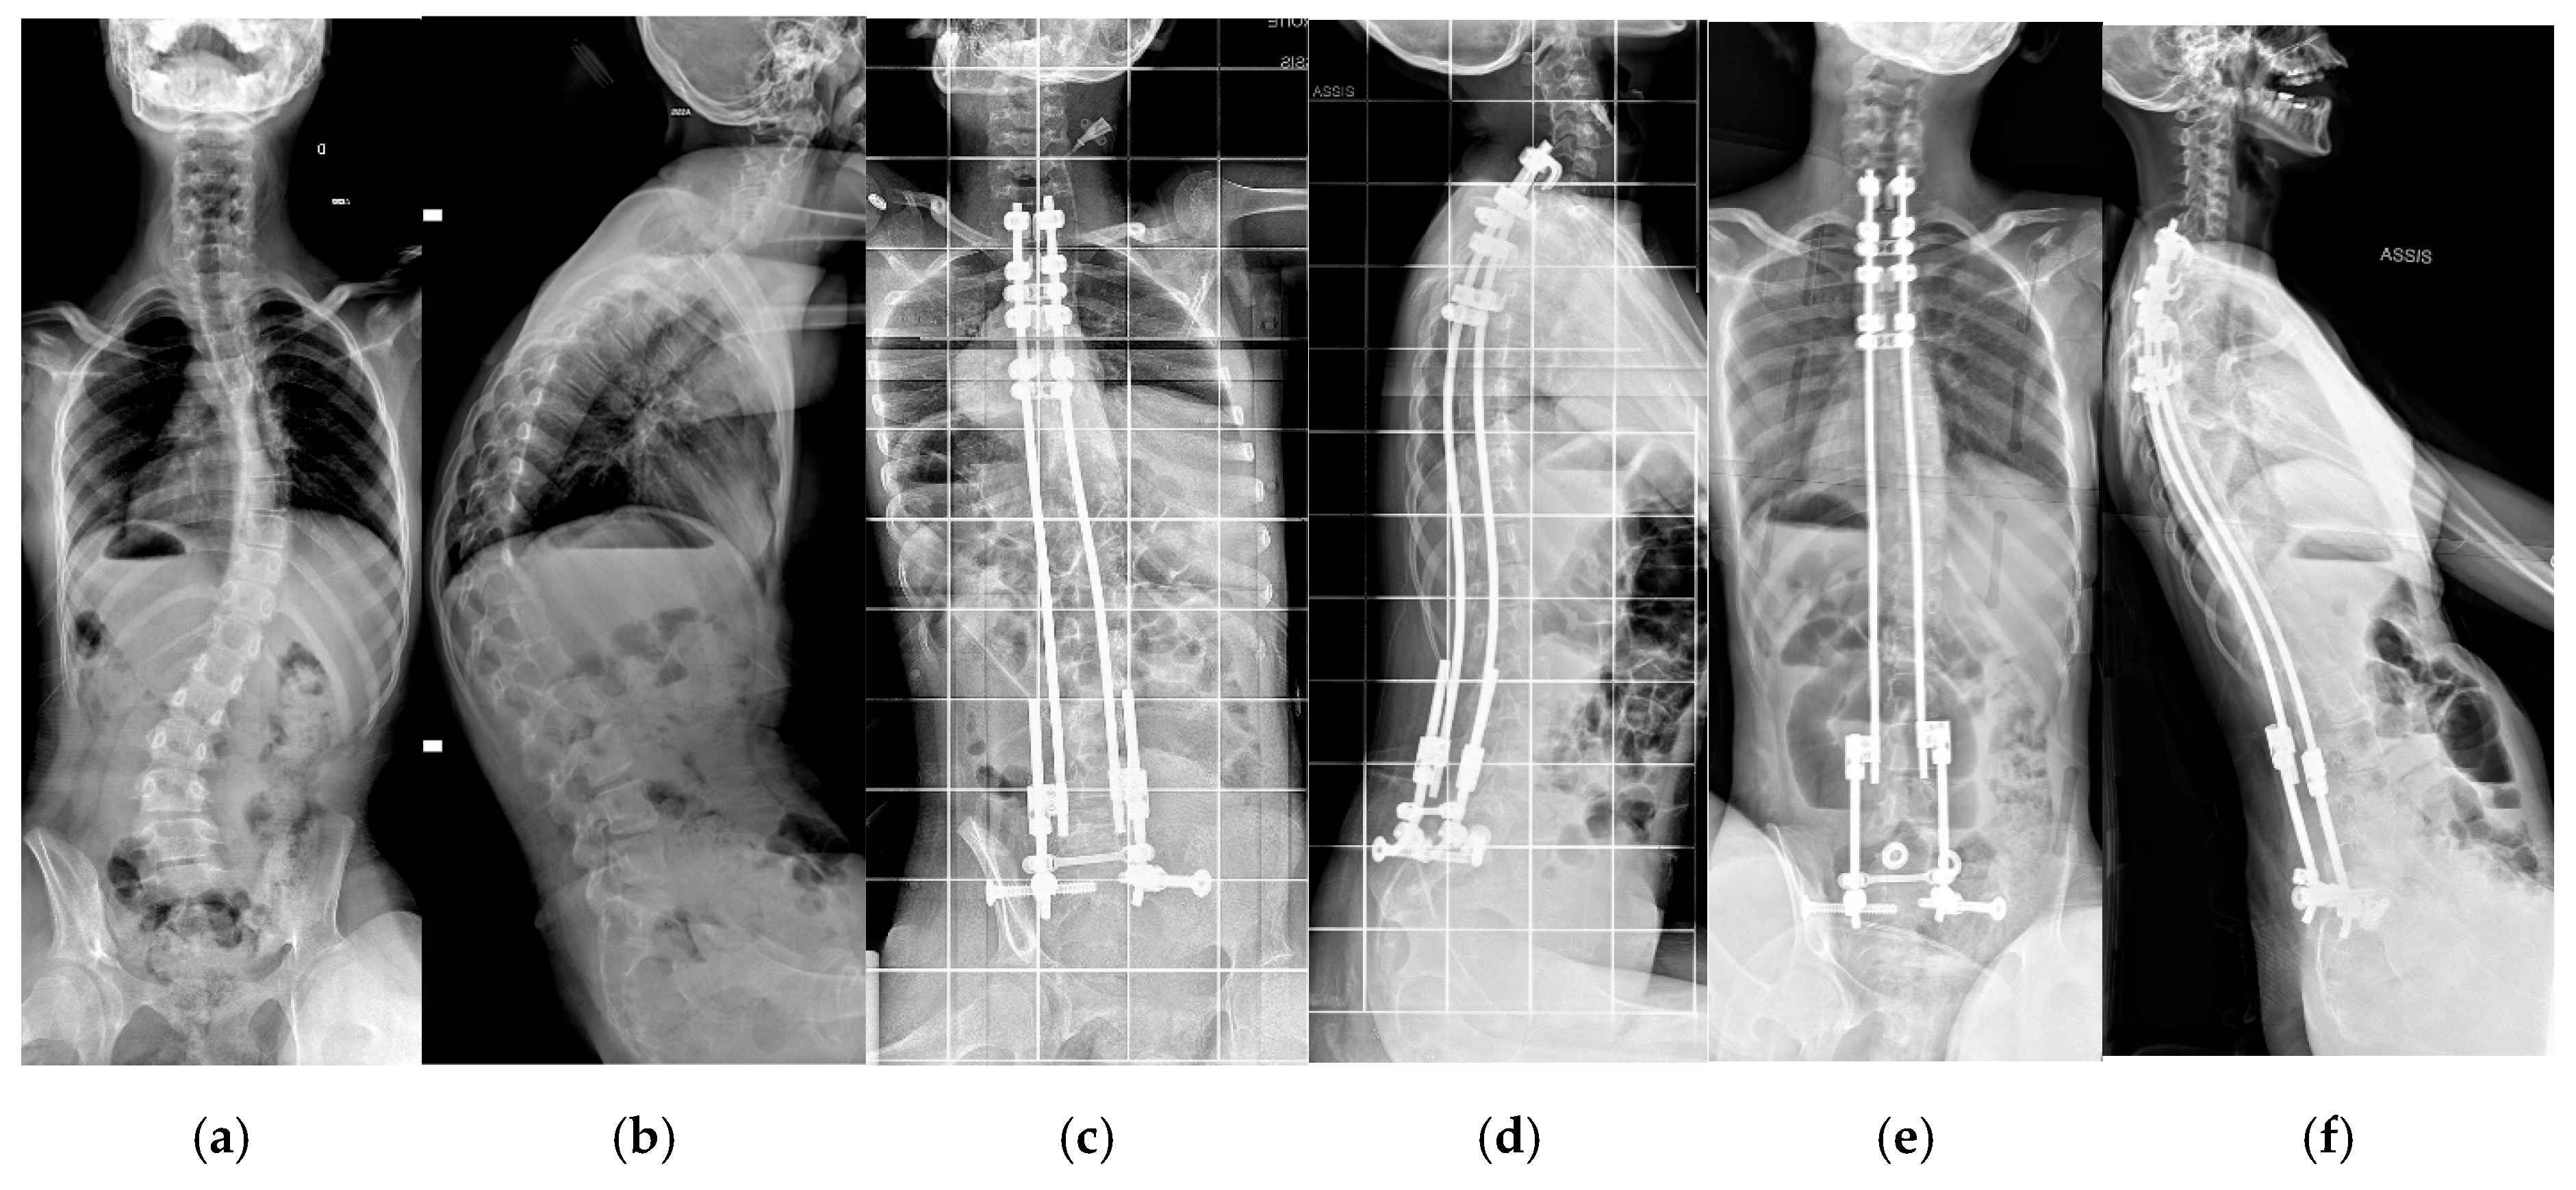

| Cobb angle, °, mean, range | 74.4 (35.2–125) | 28.9 (3.6–68.8) | <0.01 | 25.7 (5–68) | <0.05 |

| T1-S1 length, mean, cm | 31.8 (22–43.3) | 35.7 (28–41.6) | <0.01 | 36.7 (28.4–43.1) | >0.1 |

| Pelvic obliquity | 29.5 (0–100) | 9.7 (0–28.9) | <0.01 | 9.4 (0–28.2) | >0.01 |